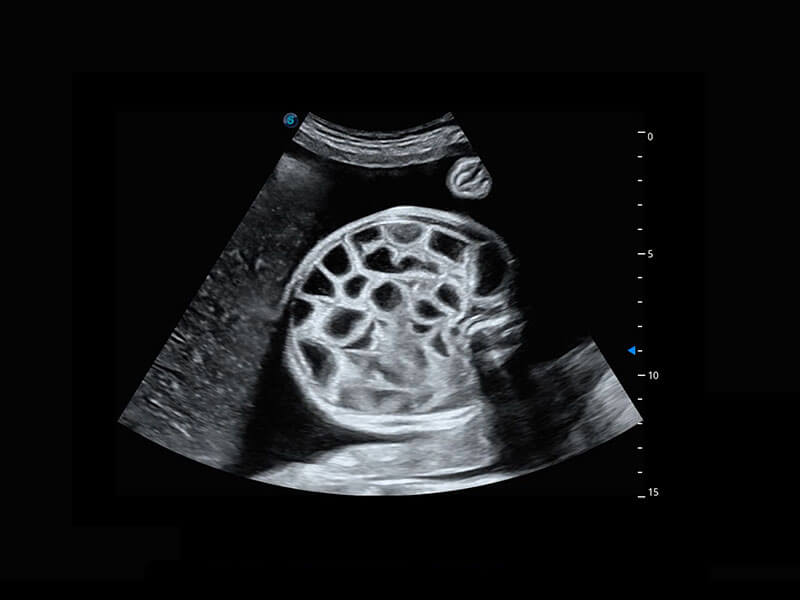

乳腺超声 / 新生儿

P60搭载宽频带线阵探头、宽景成像、弹性成像技术,为您提供乳腺应用方案。P60支持高频相控阵探头、线阵探头、腹部高频探头、腹部微凸探头等,丰富的探头群搭载敏感的彩色血流成像,适用于新生儿多种脏器检测要求,满足新生儿筛查需求。

• 新生儿肝血管癌

• 新生儿脊髓圆锥

• 新生儿心脏